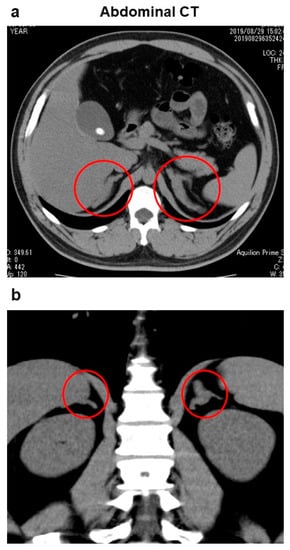

2. Case Presentation